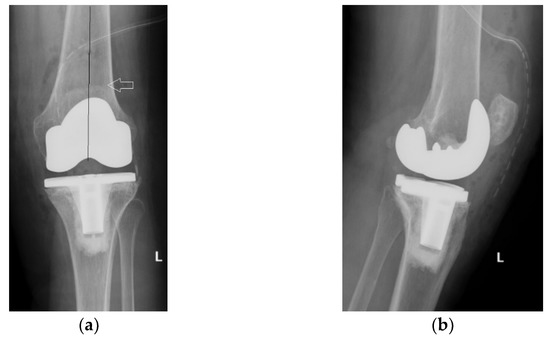

The immediate and distant postoperative evolution were favorable, as the radiological evaluation performed on the 2nd day after surgery shows; unfortunately, the lateral view is rotated (Figure 6).

Figure 6.

(a) Coronal view, patella centered on femoral axis (arrow); (b) Lateral view.

Radiological and clinical follow-up were performed at 6 weeks, 3 months and then 12 months after surgery (Figure 7, Figure 8 and Figure 9).

Figure 7.

Radiological imaging at 6 weeks after surgery: (a) Coronal view; (b) Lateral view.